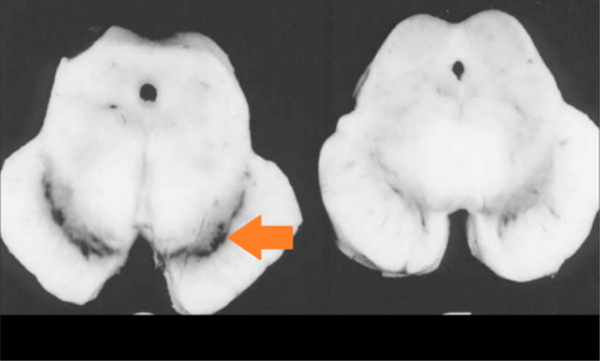

正常人及病人中脑的解剖图对比。箭头所指部位是正常人的黑质,相比之下,病人的黑质消磨丧失(来源:Memorang)